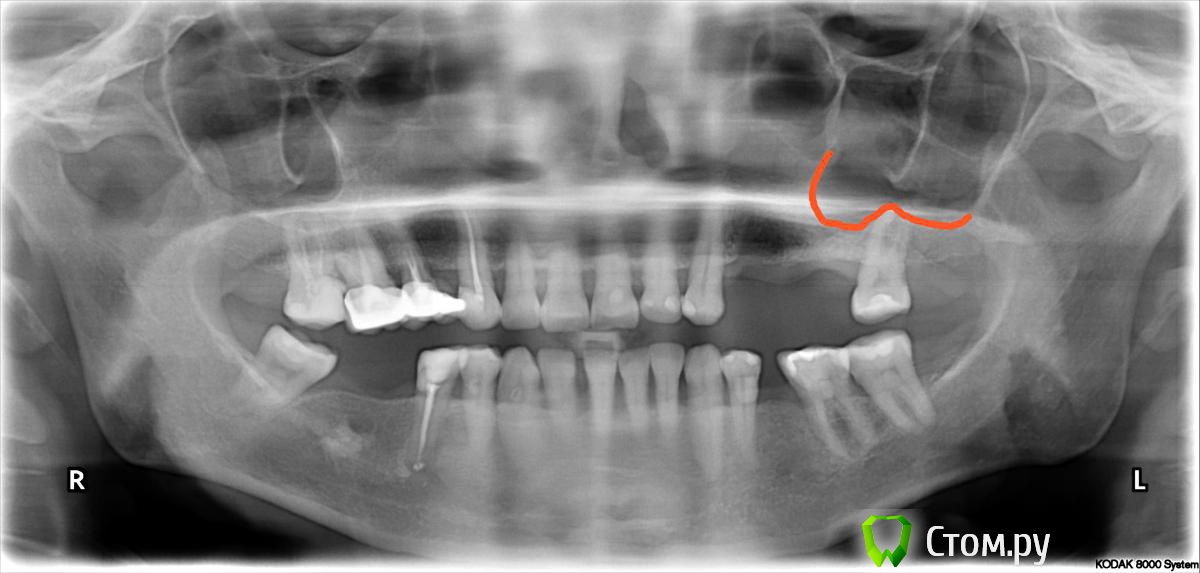

Petr_Off Опубликовано 27 мая, 2014 Поделиться Опубликовано 27 мая, 2014 В вашем случае можно было сделать аналогично .Без синуса ...Я вот тоже не очень понял зачем делали синус. По крайней мере открытый? По ОПГ ощущение, что он там не нужен. Или я ошибаюсь? Ссылка на комментарий

fmn Опубликовано 27 мая, 2014 Автор Поделиться Опубликовано 27 мая, 2014 Я вот тоже не очень понял зачем делали синус. По крайней мере открытый? По ОПГ ощущение, что он там не нужен. Или я ошибаюсь? Ошибаетесь. Ссылка на комментарий